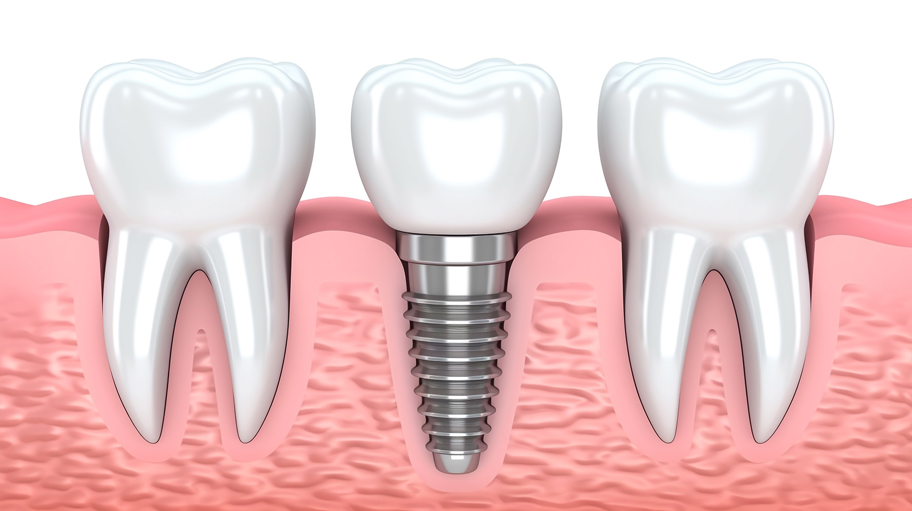

当院のインプラントメーカーについて

当院のインプラントメーカーについて 日本国内だけで50~100社のインプラントメーカーか…[続きを読む]

インプラント治療で用いる機器について

インプラント治療で用いる機器について インプラント治療は、顎の骨を削りインプラント体を埋入す…[続きを読む]